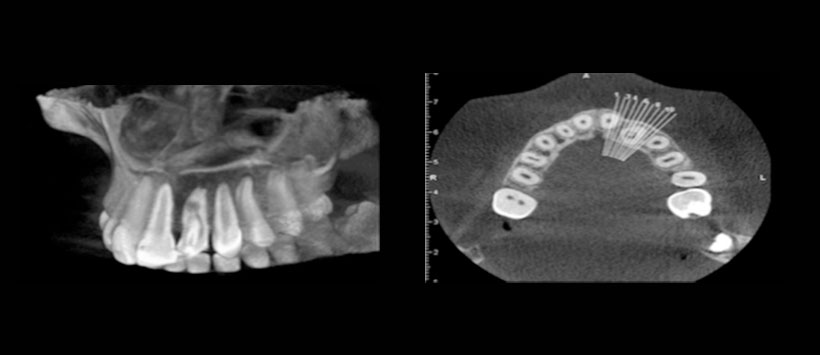

La radiografía convencional es insuficiente para el diagnóstico de la mayoría de los casos de DI debido a su presentación bidimensional de una estructura tridimensional. Por lo tanto, utilizamos CBCT para observar su extensión. Las imágenes CBCT se obtuvieron en 3 planos ortogonales (axial, sagital y coronal). CBCT produce imágenes tridimensionales de la anatomía de los dientes y sus tejidos circundantes con una exposición de radiación reducida al paciente en comparación con la tomografía medica convencional.

El presente caso es de una paciente de sexo femenino de 12 años de edad que fue derivada al departamento de manifestando dolor en el incisivo lateral superior izquierdo El examen extraoral inicial no reveló hinchazón en el lado izquierdo del maxilar. Había una fosa palatina en el diente 2.2 (Figura 1) y el diente era sensible a la palpación y la percusión. Una radiografía periapical inicial y CBCT mostraron la presencia de DI tipo 2 (Oehler) en el diente, asociado a radiolucides periapical y reabsorción de raíz interna (Figura 2). Dado que la morfología de la invaginación no era clara en la radiografía periapical, se usó CBCT para un diagnóstico y protocolo de tratamiento óptimos. El escaneo CBCT reveló dos canales separados. El canal invaginado estaba casi en el centro de la raíz, pero el otro canal estaba localizado mesiolingualmente. También se observó la reabsorción de la raíz asociada con el canal invaginado (Figura 3). El paciente fue tratado en dos sesiones. En la primera visita, se aplicó anestesia local con lidocaína al 2% que contenía epinefrina y se aisló el diente con dique de goma. La cavidad de acceso endodóntico fue preparada. Luego, la longitud de trabajo se determinó mediante radiografía periapical y el localizador de ápices. El canal invaginado se encontró fácilmente y el segundo canal se encontró usando CBCT.